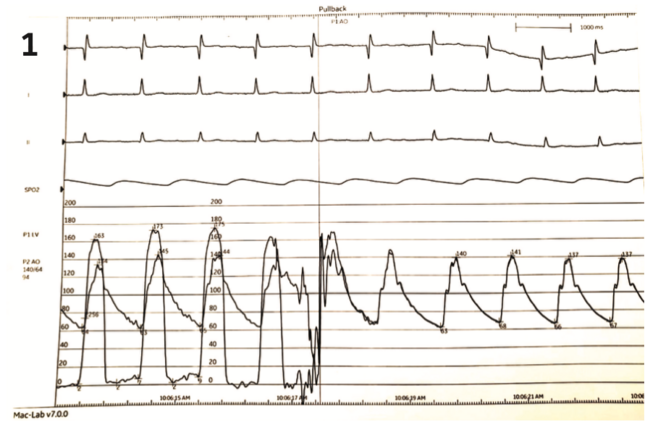

Earlier this year, when the Langston catheter (Teleflex) became unavailable due to a recall,1 those of us who love hemodynamics were left to figure out the best way to obtain invasive hemodynamic measurements for aortic stenosis. Optimal hemodynamic measurements should be sampled simultaneously from the left ventricle and the ascending aorta. In our lab, once the Langston was no longer available, we instituted simultaneous pressure measurements by accessing from both femoral arteries and using two catheters: one pigtail in the left ventricle and one in the ascending aorta. The alternative of femoral sheath side-port pressure measurement was not appealing, because of the inherent delay and resonant amplification. The pressure wire was of interest, but we were unable to get it onto our Mac-Lab hemodynamic recording system (GE Healthcare).